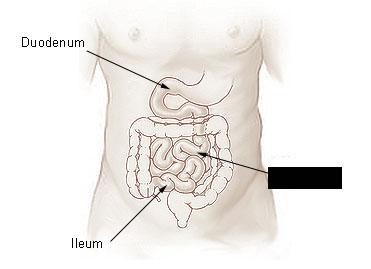

Duodenum

Ileum